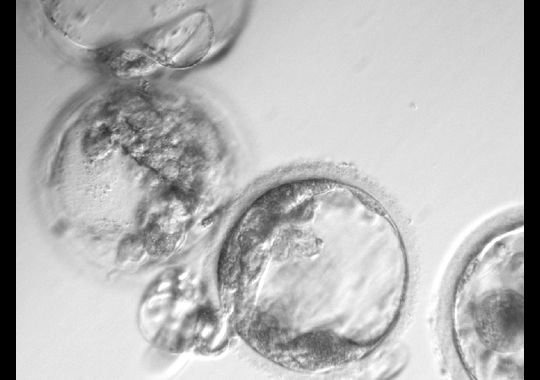

Cloned human embryo cells. (Photo: OHSU Photos)

These are the main steps of SCNT which transfer genetic material from adult skin cells into egg cells. SCNT involved preparing nucleus from a person’s skin cells and the egg cells from women that had its nucleus removed. Then insert the skin cells into an unfertilized egg cell to fuse the donor egg cells with human skin cells. Scientists using chemical compounds and electricity to induce the egg cells to behave in a similar way as normal fertilized eggs: continue to divide into other cell types which could be used for specific tissues needed. When the division yield reached 150 cells—stage called blastocyst—we could harvest the embryonic stem cells. These cells were able to develop into other types of cells and, successfully, there were no genetic material from the donor egg cell nucleus.